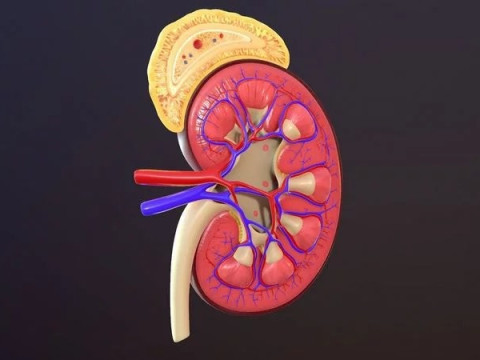

Human Kidney Low-poly Modelo 3D

Human Kidney Modelo 3D blend, jpg, fbx, max, De jack2024

human kidney renal urine organ anatomical health people anatomy biology urinary system electrolytes internal organs science medical crossNo hay comentarios sobre este artículo.